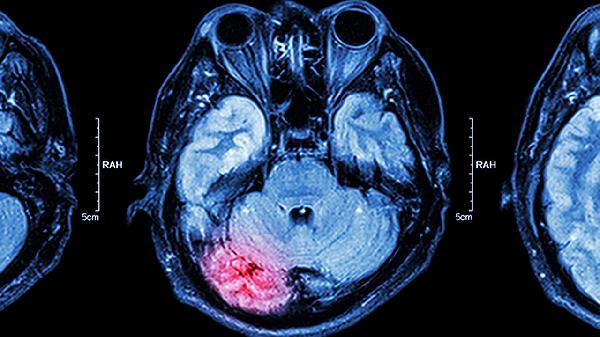

如何诊断实质性肿块:明确实质性肿块的性质需要借助医学检查。影像学检查如超声、CT或MRI可以初步判断肿块的大小、位置和形态。病理学检查如穿刺活检或手术切除后病理分析是确诊的金标准,能够明确肿块是否为肿瘤以及肿瘤的良恶性。血液检查如肿瘤标志物检测也有助于辅助诊断。